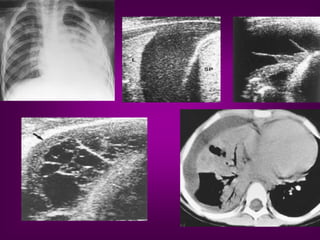

Tissue pattern representative of Alveolar

Consolidation

Presence of hyperechoic punctiform

imagesrepresentative of air bronchograms

Pleural

effusion

Lower lobe

Clinical applications of lung ultrasonography in the

intensive care unit

1. Diagnosis of pulmonary consolidation.

2. Diagnosis of atelectasis

3. Diagnosis of alveolar-interstitialsyndrome

4. Differentiating between pulmonary oedema and ARDS

5. Differentiating between pulmonary oedema and COPD

6. Diagnosis of pulmonary embolism

7. Diagnosis of pneumothorax

8. Diagnosis and estimation of volume and nature of pleural effusion.

9. Diagnostic and therapeutic ultrasound-guided thoracentesis.